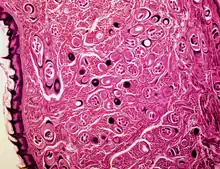

The larvae travel by capillaries to various organs, such as the retina, myocardium, or lymph nodes; however, only larvae that migrate to skeletal muscle cells survive and encyst.[14] The larval host cell becomes a nurse cell, in which the larva will be encapsulated, potentially for the life of the host, waiting for the host to be eaten. The development of a capillary network around the nurse cell completes encystation of the larva. Trichinosis is not soil-transmitted, as the parasite does not lay eggs, nor can it survive long outside a host.[5][21]